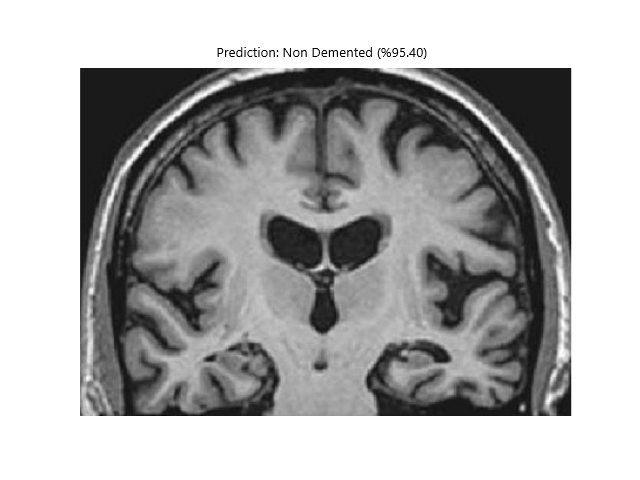

def show_image_with_prediction(image_path, prediction, confidence, class_names):

image = Image.open(image_path)

plt.imshow(image)

plt.title(f"Tahmin: {class_names[prediction]} (%{confidence * 100:.2f})")

plt.axis('off')

plt.show()

def show_image_with_prediction(image_path, prediction, confidence, class_names):

image = Image.open(image_path)

plt.imshow(image)

plt.title(f"Prediction: {class_names[prediction]} (%{confidence * 100:.2f})")

plt.axis('off')

plt.show()

- Vbai-1.0 Dementia => (Accuracy rate at least in all probability = 90%) (DEMENTIA STATES)